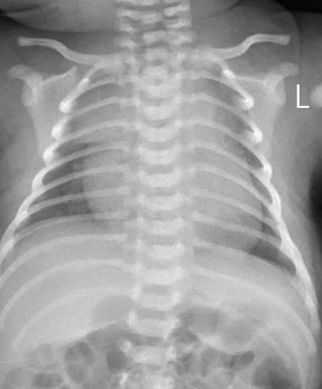

①胸部X线:心影多呈普遍性扩大,肺纹理增多,肺门或肺门附近阴影增加,肺部淤血

✦ Case 1,新生儿,急性心力衰竭,心肌炎,细小病毒感染

一般治疗:镇静(水合氯醛×2d)、吸氧

心脏治疗

— 减轻心脏负荷:呋塞米 0.5-1mg/kg iv;出入量维持负平衡,每日负100-200ml

6个月复查CMR

入院时CMR可见右室明显增厚,经积极治疗,6个月复查右室心肌厚度基本恢复正常